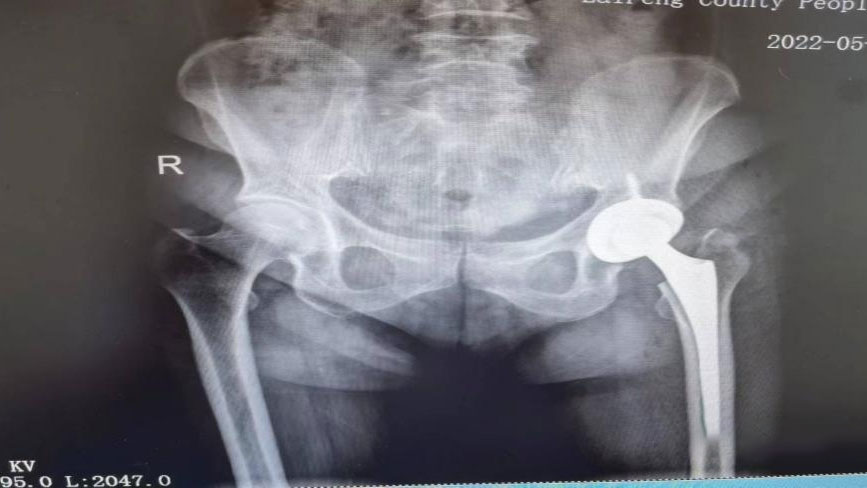

术后复查图片

骆渊城副院长亲自主刀为向奶奶开展了Bikini切口微创髋关节置换术。与常规手术相比,主要是通过path髋臼挫手柄进行分体式操作,通过改善切口为比基尼切口,在不挤压远端切口皮肤的情况下,避开股骨的阻挡,使髋臼挫进出非常方便简单,出血更少,损伤更小。因不牵拉伤任何肌肉,病患软组织损伤减小,术后康复更快捷,疼痛感更轻。向奶奶手术1个半小时顺利结束,术后状态良好,第二天不需用任何辅助工具便自由下床活动。目前,向奶奶恢复良好。

据主刀医生骆渊城介绍,Bikini切口微创全髋关节置换术的优点是创伤小、康复快等,更重要的是术后髋脱位风险极低,术后无任何避免下蹲、翘腿等体位禁忌,可以更快更好地回归正常工作及生活。这个手术还兼顾美观,女性患者穿比基尼看不到手术切口疤痕,也称“比基尼切口”。